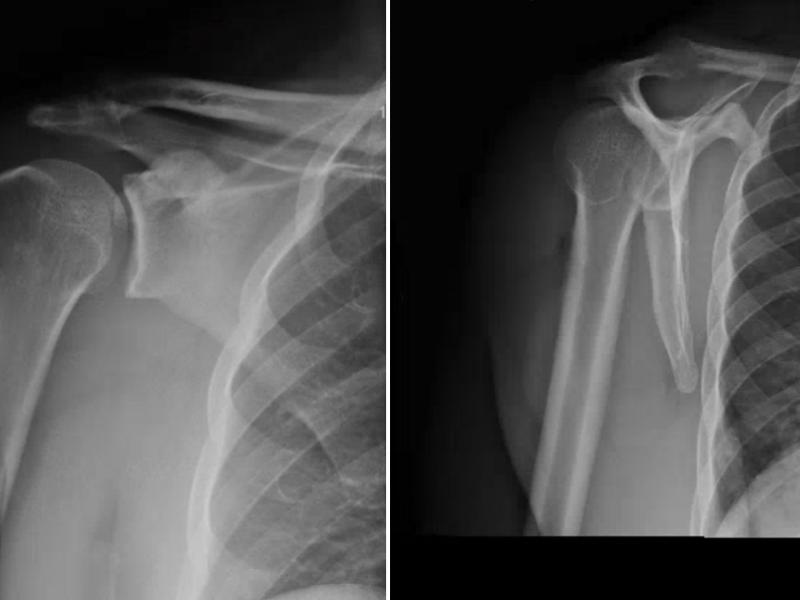

A 42 yo male presents to the ED after he was assaulted. He